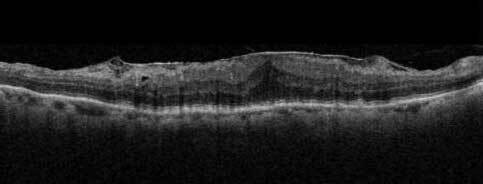

黄斑上膜ができ、黄斑にしわができた断層写真

黄斑は視力にとって最も重要な部分で、文字を読んだり、顔を認識したりする中心視力を司っています。黄斑以外ははっきりと見えているのでは無く、ぼーっと見えているだけで、文字を読んだりするような視力はありません。黄斑上膜が形成されると、この膜が収縮することで黄斑部の網膜にしわやゆがみが生じ、視機能に様々な影響を及ぼします。